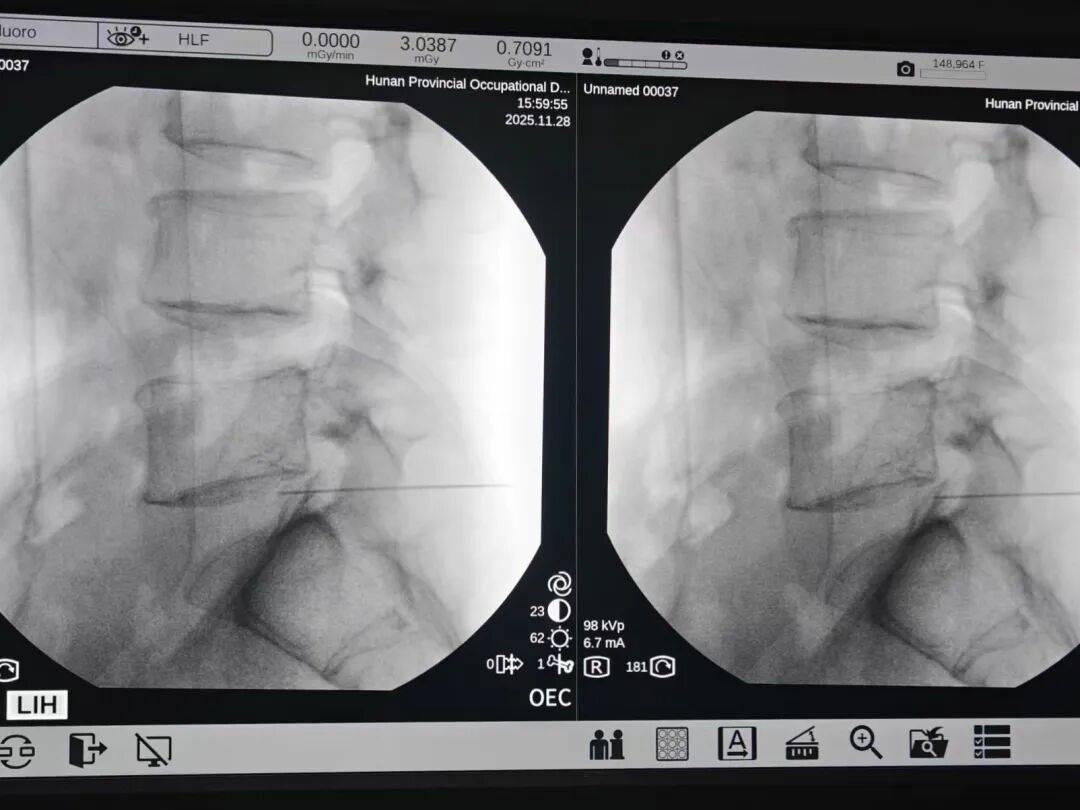

湖南省职业病防治院(南华大学附属职业病防治院)就诊后,彭先生被确诊为 腰椎间盘突出。考虑到他需要长期驾驶的职业特性,且保守治疗效果不佳,医生建议行 “腰椎射频消融术”。手术当天,他的腰痛即明显缓解。彭先生感叹:“原来以为一定要开刀,没想到微创也能解决问题!”

对于因腰椎间盘突出引起、且保守治疗无效的腰痛,射频消融术是一种针对性强的微创解决方案。它尤其适合需快速返岗的久坐族,其核心优势源于独特的 “精准热疗” 机制。

正因为创伤极小(仅一个针眼)、目标精准,手术通常在30-60分钟内完成,且仅需局部麻醉,术后当天疼痛显著缓解,次日即可下床活动,约两周可恢复驾驶、伏案等轻体力工作,完美契合久坐族快速回归生活和工作的需求。